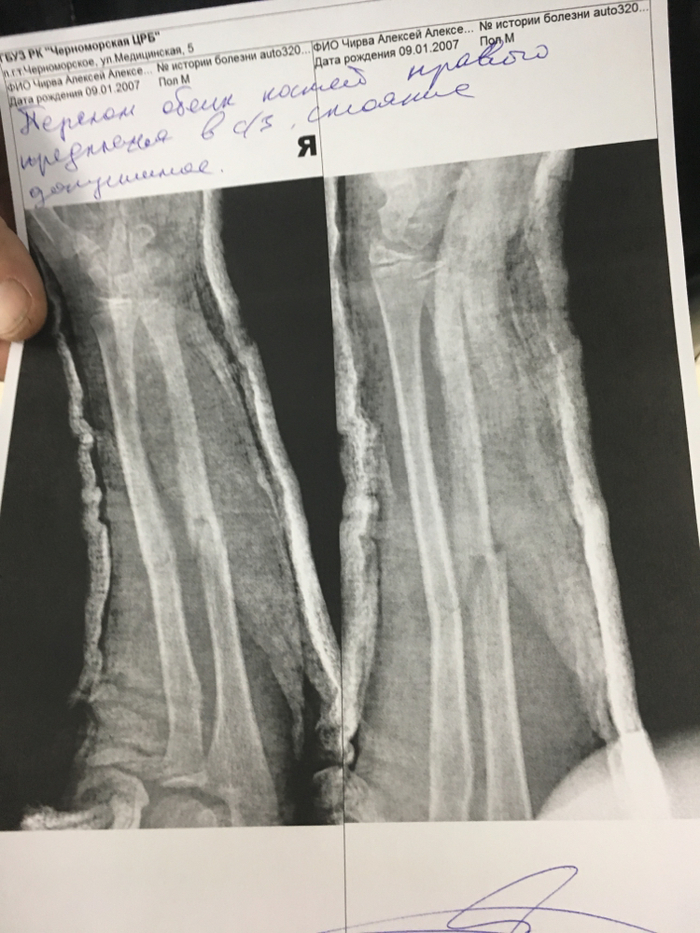

Вот рентген:

вывих,

вправлен (виден отлом бугорка),

и после того, как болтами зафиксировали бугорок.